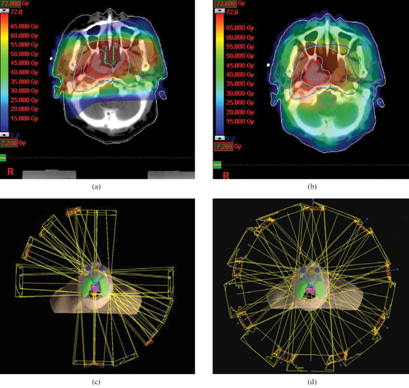

至於調強適形放射治療,是在三維適形放射治療基礎上演進而來。在每個放射束(照射野)內分為許多子野,子野的放射強度是不一樣的(故稱為調強)。過程中劑量的計算,採用逆向設計治療計劃,全部由電腦負責,使腫瘤劑量適形性更好,特別對於不規則形腫瘤或腫瘤附近有重要組織器官需要保護的病例,調強適形放射治療比三維適形放射治療有更好的優勢。

以上是鼻咽癌治療的劑量分佈圖,二維和三維適形治療的高劑量區未能很好地覆蓋目標腫瘤區域(紅框區域),而二維治療中,腮腺受到很高的劑量,而調強適形治療既能將高劑量準確地投放在目標腫瘤區域,也能減少腮腺的劑量。

調強適形放射治療主要適合於前列腺癌、鼻咽癌、頭頸癌、甲狀腺癌、腦癌、乳腺癌、肺癌、胰腺癌等。應用調強適形放射治療能夠進一步提高腫瘤內劑量,降低附近正常組織的劑量,提高療效,減少副作用和後遺症,提升病人治療後的生活質素。如調強適形放射治療前列腺癌,可使病灶劑量由68Gy提高到81Gy,3年控制率由48%提高到94%,直腸副作用由57%降為2%;調強適形治療鼻咽癌可保護腮腺減低口乾程度,對於接近眼睛或視神經的鼻咽腫瘤,則能避免放射線對視力的影響。